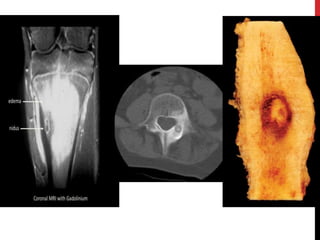

CHONDROBLASTOMA

It is rare type of benign tumor.

Genatic /signaling problem

It is appear in epiphysis usually in proximal humrus, femur or tibia.

Presenting with aching & tenderness adjacent joint. Fluid buildup

and affect motion

most chondroblastomas are small, well-marginated lesions, a small

subset of chondroblastomas behave in a much more aggressive

fashion. Some nonetheless become very large or have the capability

of metastasizing to the lungs and soft tissues.

TREATMENT

It requires surgery by scraping out and filling of

the cavity with bone grafting .